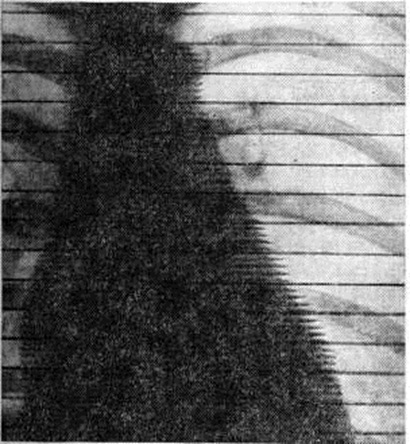

При поражении лёгких рентгенологически в базальных отделах определяется диффузный и кистозный пневмосклероз (смотри полный свод знаний), часто сочетающийся с умеренной эмфиземой лёгких (смотри полный свод знаний), а также признаки адгезивного (спаечного) плеврита (смотри полный свод знаний).

Рентгенологические симптомы поражения сердца выявляются почти в 100% наблюдений и характеризуются изменениями его конфигурации за счёт увеличения размеров левого желудочка и правых отделов (вследствие развития пневмосклероза и лёгочной гипертензии). Типичным является уменьшение амплитуды пульсации вплоть до зон адинамии (рисунок 6), хорошо выявляемое при рентгенокимографии (смотри полный свод знаний). Могут наблюдаться признаки поражения клапанного аппарата, преимущественно в виде недостаточности левого предсердно-желудочкового (митрального) клапана, в отдельных случаях— стеноза левого предсердно-желудочкового отверстия и недостаточности клапана аорты (изменения конфигурации, размеров полостей сердца, а также и характера пульсации сердца).